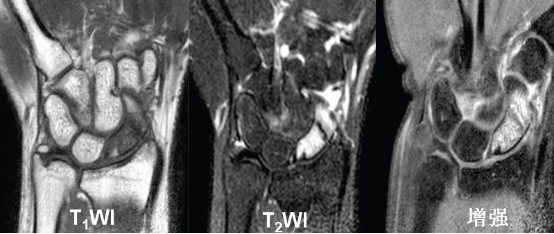

舟月骨缺血性坏死

腕关节发生骨缺血坏死的常见部位为舟骨和月骨

好发于20-30岁手工劳动者,也常见于腕部急性创伤和月骨骨折脱位后

男性多见

X线表现为病变早期骨形态尚可,骨质密度增高,其内可见囊样透亮影,进展期骨质塌陷,周边关节间隙增宽;MR对早期骨缺血坏死较敏感

舟骨缺血性坏死

54Y,M 月骨缺血性坏死

65Y,M,左手疼痛2个月